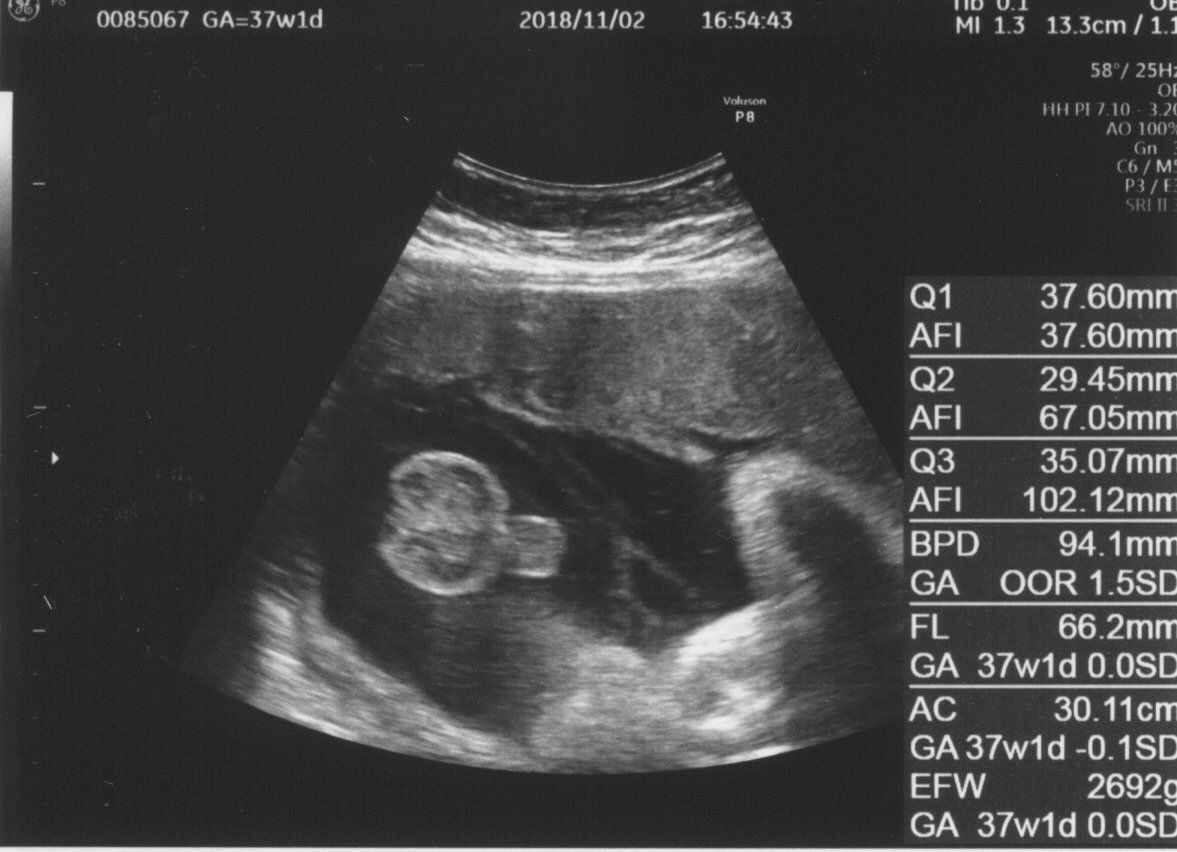

妊娠37週目 いつ生まれてきても大丈夫

赤ちゃんのEFW(推定児体重)も順調に増え、先生からも「いつ生まれても大丈夫だね」とのお墨付きが!

エコー写真1枚にはとてもおさまらないくらい大きくなった赤ちゃんは、「元気な男の子だよ」とアピールしてくれました。